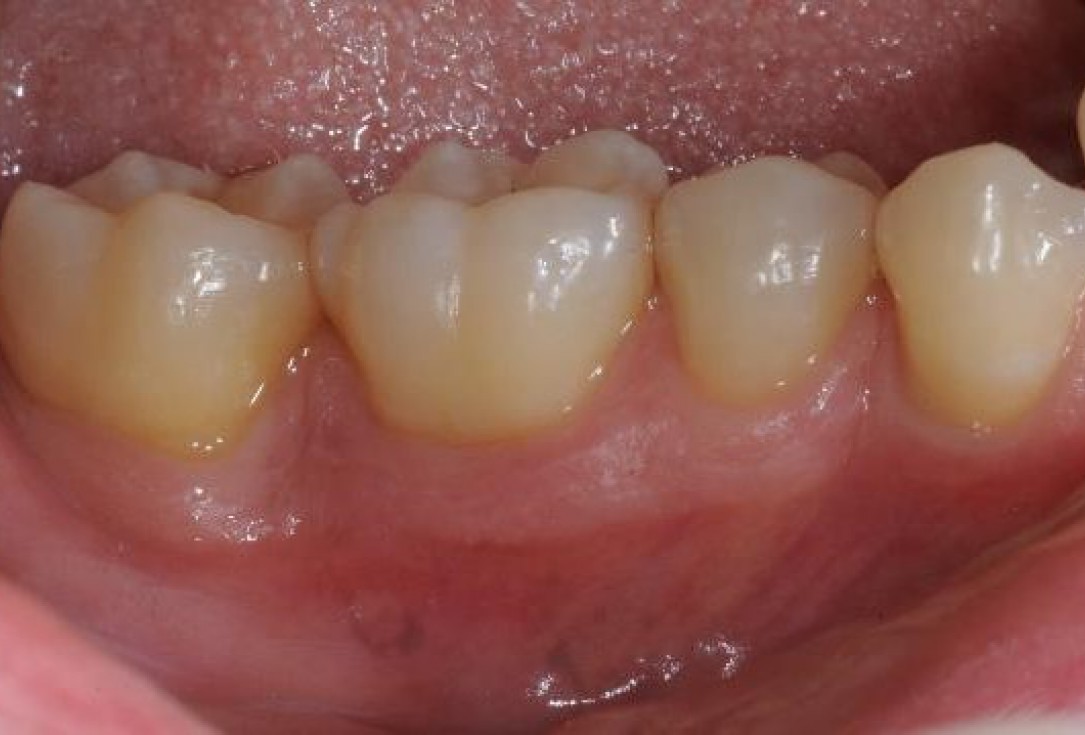

Pre-operative clinical situation. Shallow multiple adjacent gingival recessions in the first quadrant.